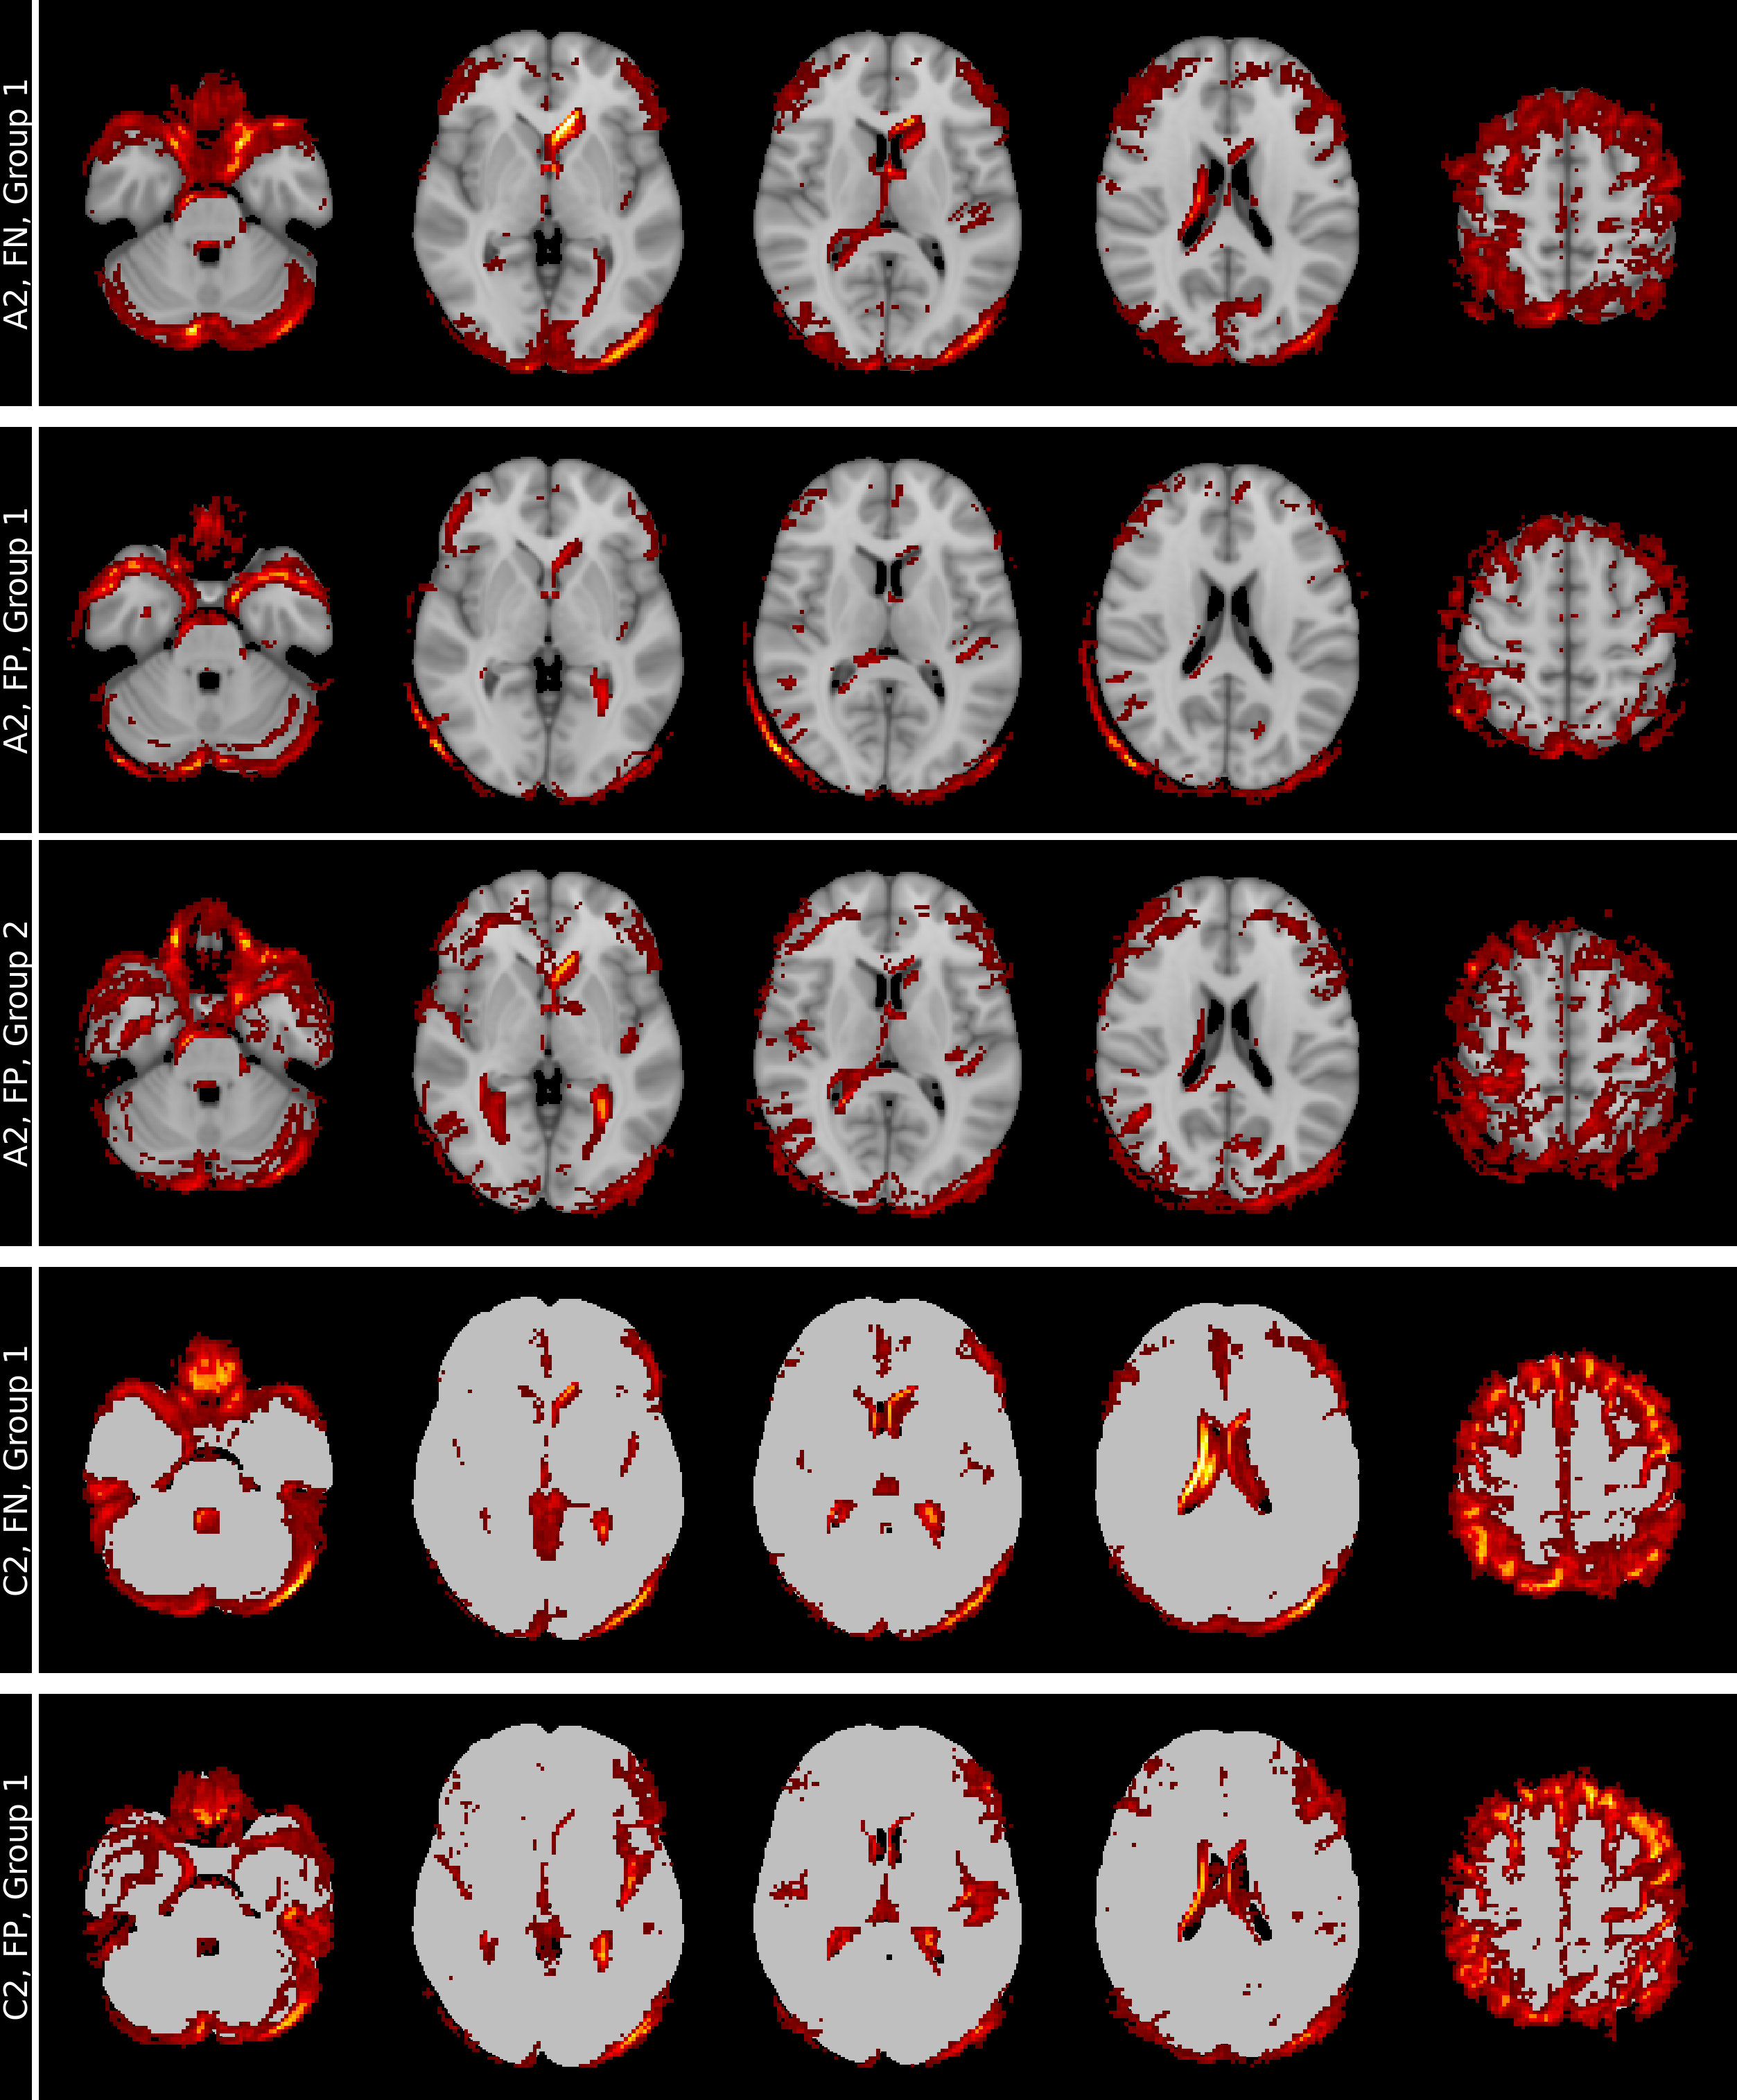

Figure 3 shows mean heatmaps for classification decisions on test images. Skull stripping enhances classification accuracy, while mean heatmaps from binarized inputs closely resemble those from non-binarized inputs.

Heatmaps from the skull-stripped model (A2) serve as the reference for structural heatmap comparisons in Table 3. Skull-stripped binarization (B2, C2, D2) shows lower voxel-wise dissimilarity (RMSE), higher global similarity (Pearson Correlation), and improved localized similarity (MSSIM, EMD) compared to the aligned versions (A1, B1, C1, D1). Among the binarized models, skull-stripped-binarization-13.75% (B2) demonstrates the highest overall structural similarity (RMSE, Pearson Correlation, MSSIM, EMD) with the reference (A2), while skull-stripped-binarization-27.50% exhibits the strongest regional overlap with the reference. These results emphasize the dominant role of volumetric features over T1w contrast variations.

Refer to caption

Figure 3: Mean heatmaps from test images: Left column with (A1) aligned T1w MRI, identical binarized T1w image with threshold levels (B1) 13.75%, (C1) 27.50% (C1) and (D1) 41.25%, and right column with corresponding skull-stripped versions (A2, B2, C2, D2). The mean accuracies of the models are shown in yellow.

Figure 5: Mean heatmaps for the groups identified using the individual heatmaps and spectral clustering for misclassifications of models A2 and C2. Model A2 (skull-stripping) shows a clear separation between False Negative (row 1, Group 1) and False Positive (row 2, Group 1) in the shape of the temporal lobe (column 1). In row 3 (A2, False Positive, Group 2) the ventricles are more pronounced (column 2) compared to heatmaps for False Negative analysis in row 1. Comparison of model C2 shows also differences in the temporal lobes, the ventricles and the cortex. Note. FN: False Negative, FP: False Positive.